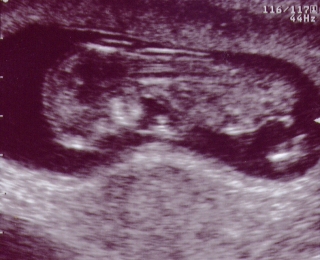

Here's my first picture. The technician is estimating that I am 8 weeks along at this point. I'm pretty small, but I'm growing fast. |  This is me at 12 weeks. Now you can see some of my body parts. It looks like I'm upside down because I am facing Mommy's back. I was too camera shy to turn around. I am just over 6 cm long -I still have a lot of growing to do to catch up to my big sister. |